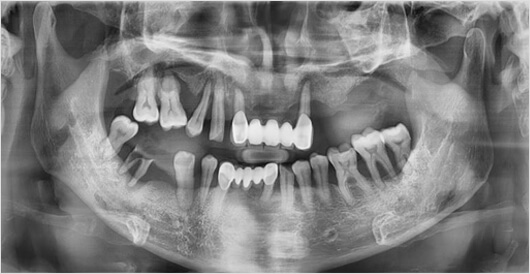

네비게이션 임플란트

0.1mm의 오차도 허용하지 않는 정확함